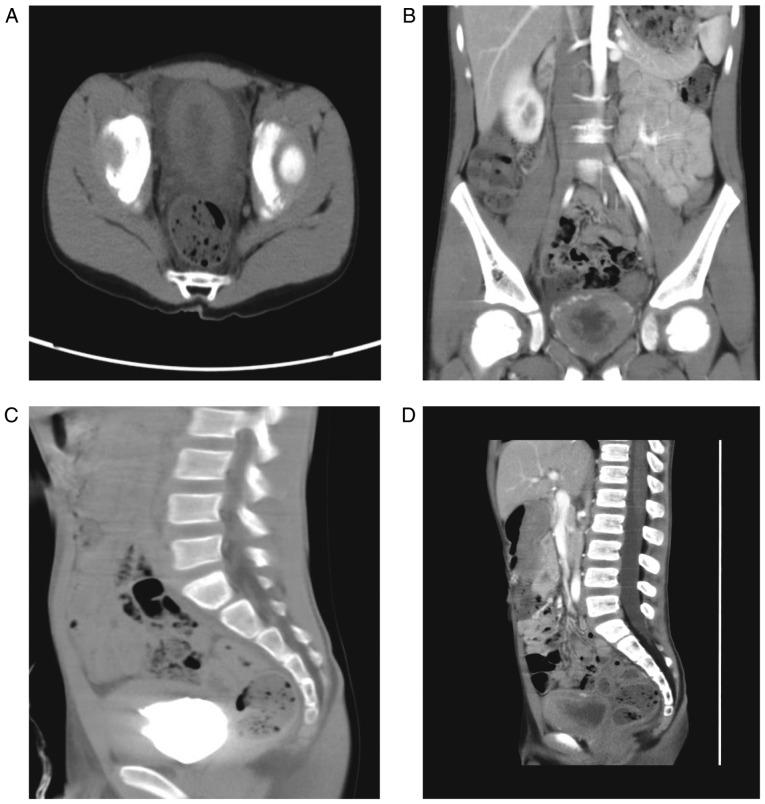

The aim of the present case report was to investigate the clinical features, pathological examination and treatment of eosinophilic cystitis (EC) in children. Two cases of EC were reported and reviewed from January 2016 to March 2017. Case 1 (male; 6 years old) had intermittent hematuria, frequent urination, urgent urination, difficulty in urination and abdominal pain. Case 2 (male; 7 years old) had frequent urination, urgent urination, urinary pain, dysuria and suprapubic pain with no hematuria. One patient had a history of allergies and both patients underwent a cystoscope biopsy. Blood eosinophils were clearly increased and a bone marrow biopsy examination revealed that marrow eosinophils were also increased in both cases. The urine culture results were negative. Ultrasonography and computed tomography revealed uneven thickening of the bladder wall and diffusive mucosal lesions. Cystoscopy revealed that the bladder volume became smaller and the mucosa at the bladder floor and neck was red. Lesions were biopsied through the urethra and the following characteristics were observed: Congestion and edema of the bladder mucosa, infiltration of the blood vessels and eosinophils in the muscular layer, accompanied by focal muscle necrosis. Patient 1 was administered anti-inflammatory and cetirizine hydrochloride treatments, followed by 6 weeks of prednisone dose-reduction therapy. Patient 2 was administered antibiotics and cetirizine hydrochloride. Following 6-month follow-ups, abnormal voiding symptoms had disappeared in each case. Ultrasonography and computed tomography revealed no bladder wall thickening or space-occupying lesions. EC in children is rare and easily misdiagnosed as nonspecific bladder inflammation or bladder occupying lesions. Cystoscopy and biopsy are necessary to diagnose EC and conservative treatments with anti-inflammatory, anti-allergic and cortical hormone nonspecific treatments are suggested.

本病例报告的目的是探讨儿童嗜酸性膀胱炎(EC)的临床特征、病理检查及治疗方法。报告并回顾了2016年1月至2017年3月期间的2例EC病例。病例1(男,6岁)有间歇性血尿、尿频、尿急、排尿困难及腹痛症状。病例2(男,7岁)有尿频、尿急、尿痛、排尿困难及耻骨上疼痛,无血尿症状。1例患者有过敏史,2例患者均接受了膀胱镜活检。两例患者血液嗜酸性粒细胞均明显增多,骨髓活检显示骨髓嗜酸性粒细胞也增多。尿培养结果为阴性。超声和计算机断层扫描显示膀胱壁不均匀增厚及弥漫性黏膜病变。膀胱镜检查显示膀胱容量变小,膀胱底部和颈部黏膜发红。通过尿道对病变进行活检,观察到以下特征:膀胱黏膜充血水肿,肌层血管及嗜酸性粒细胞浸润,伴有局灶性肌肉坏死。患者1接受抗炎及盐酸西替利嗪治疗,随后进行6周的泼尼松减量治疗。患者2接受抗生素及盐酸西替利嗪治疗。经过6个月的随访,两例患者的排尿异常症状均消失。超声和计算机断层扫描显示无膀胱壁增厚或占位性病变。儿童EC较为罕见,易被误诊为非特异性膀胱炎症或膀胱占位性病变。膀胱镜检查及活检对于诊断EC是必要的,建议采用抗炎、抗过敏及皮质激素等非特异性保守治疗方法。